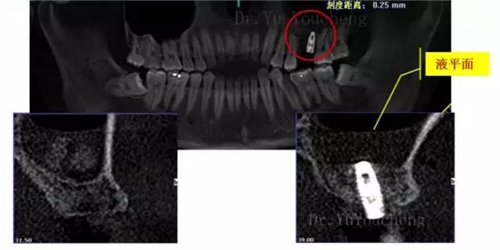

系列課開播前小編為大家預(yù)告了一例上頜竇外提升術(shù)后種植體方向改變的病例,當(dāng)時(shí)頓生種種疑惑:“真的么?怎么會(huì)?怎么辦!!”在本次課程中余教授給出了答案:上頜竇外提升同期種植有一重要的因素,即種植體初期穩(wěn)定性的獲得。該患者由于其骨量的嚴(yán)重不足,雖然可通過大直徑覆蓋螺絲保證種植體不至于滑落,但隨著竇粘膜的運(yùn)動(dòng)和部分移植骨的吸收,種植體方向最終受到了影響,這也提示我們在制定治療計(jì)劃過程中應(yīng)慎重考慮這一因素,以確保更好的種植預(yù)后效果。